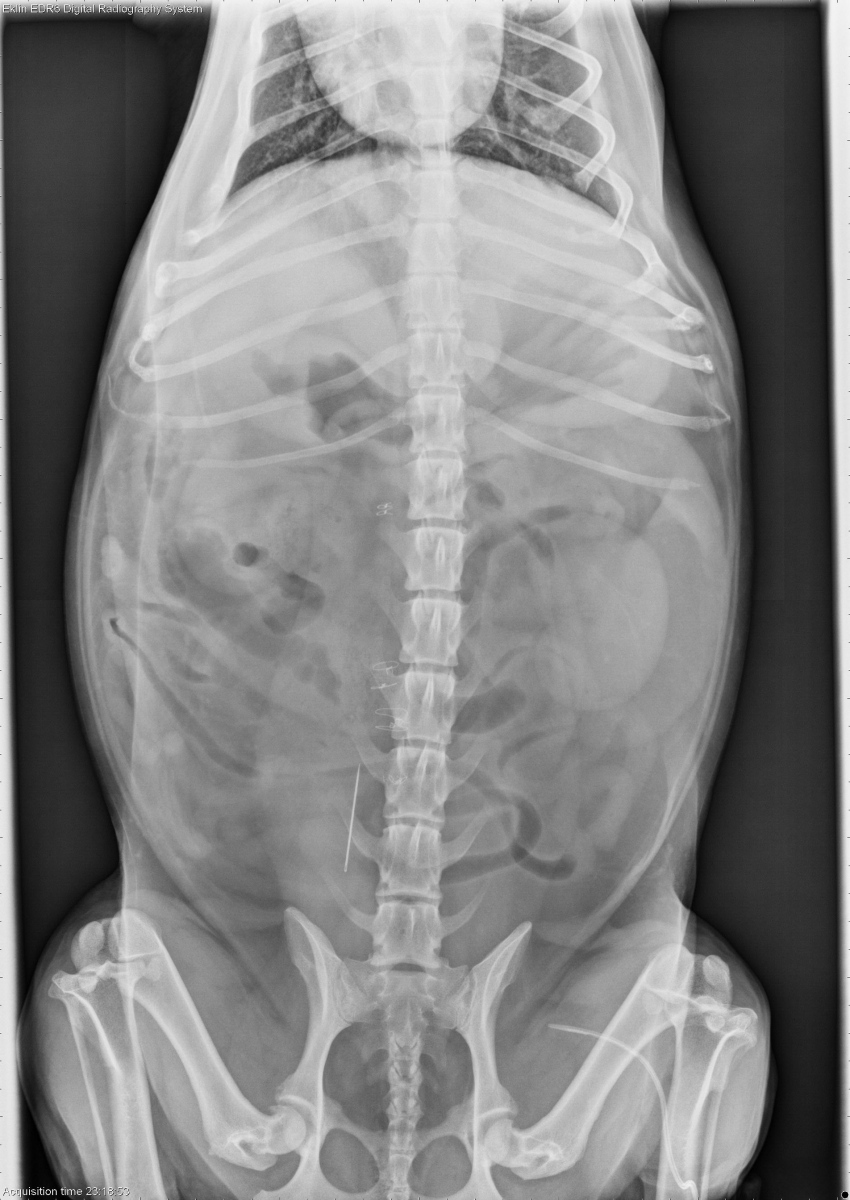

Today’s case is a 10 year old female neutered Corgi with several days of vomiting and anorexia. What is the most important finding?

VD Abdomen

Findings

The liver is mildly enlarged with rounded margins. The stomach is mildly distended with fluid and gas. On the ventrodorsal projections, the duodenum is moderately distended with fluid and gas, with several unusual gas bubbles. There is a soft tissue-gas interface at the caudal duodenal flexure. The remainder of the small intestine is normal in diameter. A metallic sewing needle is present in the retroperitoneal space. No abnormalities are noted in the spleen or urinary tract. Radiopaque sutures are present in the ventral abdominal wall.

Duodenal foreign body (corn cob).

An ultrasound examination was performed to confirm the location of the foreign body. The duodenum was distended with fluid proximal to the clean-shadowing foreign object, and returned to normal diameter distal to it. A laparotomy was performed to remove both the foreign body and the sewing needle. The liver biopsy showed vacuolar hepatopathy.